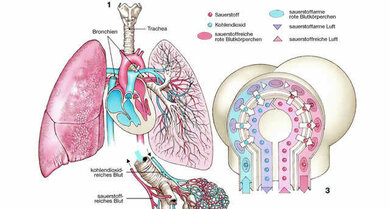

Als Atemwege bezeichnen Mediziner alle Körperteile, die beim Ein- und Ausatmen von Luft durchströmt werden: Durch Mund und Nase gelangt die Luft über den Rachen in die Luftröhre. Die Luftröhre liegt hinter dem Brustbein und teilt sich im Brustkorb in einen linken und einen rechten Hauptbronchus. Diese führen gemeinsam mit den jeweiligen Lungengefäßen zum linken beziehungsweise rechten Lungenflügel.

Die Lunge (lateinisch: Pulmo) ist nämlich paarig angelegt. Jeder der beiden Lungenflügel wird über eigene Gefäße versorgt und hat mit dem jeweilgen Hauptbronchus auch eine eigene Luftzufuhr, welche gemeinsam mit den Venen und Arterien am sogenannten Lungenhilus in die Lunge eintritt. Der linke Lungenflügel ist etwas kleiner als der rechte und besteht auch nur aus zwei statt aus drei Lungenlappen, da in seiner Nähe das Herz liegt und ihm damit weniger Raum zur Verfügung steht. Jeder Hauptbronchus teilt sich entsprechend der Anzahl der Lungenlappen in sogenannte Lappenbronchien und verästelt sich dann weiter in Segementbronchien und immer kleinere Bronchien und Bronchioli, bis am Ende die kleinen Lungenbläschen, die sogenannten Alveolen stehen.

Sie sind der Ort, an dem die Lunge ihre wichtigste Funktion, den Gasaustausch wahrnimmt und geben dem Lungengewebe sein schwammartiges Aussehen.

Die wichtigste Aufgabe der Lunge ist der Gasaustausch. Da unser Körper viel Sauerstoff benötigt und auch entsprechende Mengen an Kohlenstoffdioxid ausscheiden muss, ist dafür eine große Fläche notwendig. Diese bieten die Lungenbläschen. Sie verfügen über besonders dünne Wände, die quasi direkt an die Blutgefäße grenzen. Dadurch ist es möglich dass der Sauerstoff aus der Atemluft durch diese Wände in das sauerstoffarme Blut der Lungengefäße übergeht, während das Kohlendioxid aus dem Blut in die Alveolen gelangt.

In den Lungenbläschen wird das sauerstoffarme Blut wieder mit dem lebensnotwendigen Stoff angereichert

© ddp Images GmbH/Picture Press/wissenmedia